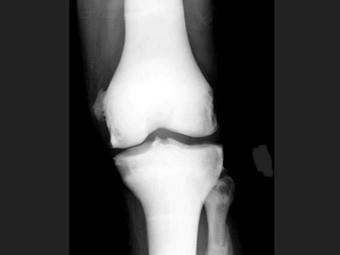

男,21岁,曾多次有过骨折史,结合图像,最可能的诊断是?(?)A.石骨症B.成骨不全C.畸形性骨炎D.转移性骨肿瘤E.氟骨症

问题 男,21岁,曾多次有过骨折史,结合图像,最可能的诊断是?(?)

选项 A.石骨症 B.成骨不全 C.畸形性骨炎 D.转移性骨肿瘤 E.氟骨症

答案 A